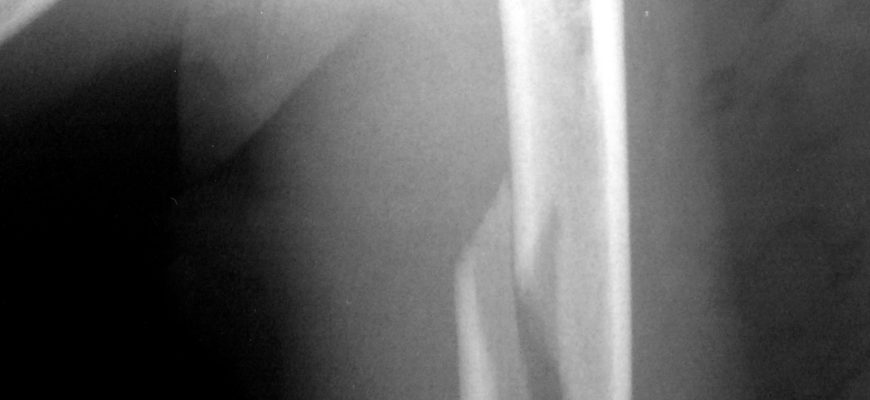

- Проходит рентгенологическое обследование.

Рентген — один из методов диагностики перелома плечевой кости.

Если результаты рентгенологического исследования малоинформативны, назначается компьютерная томография.